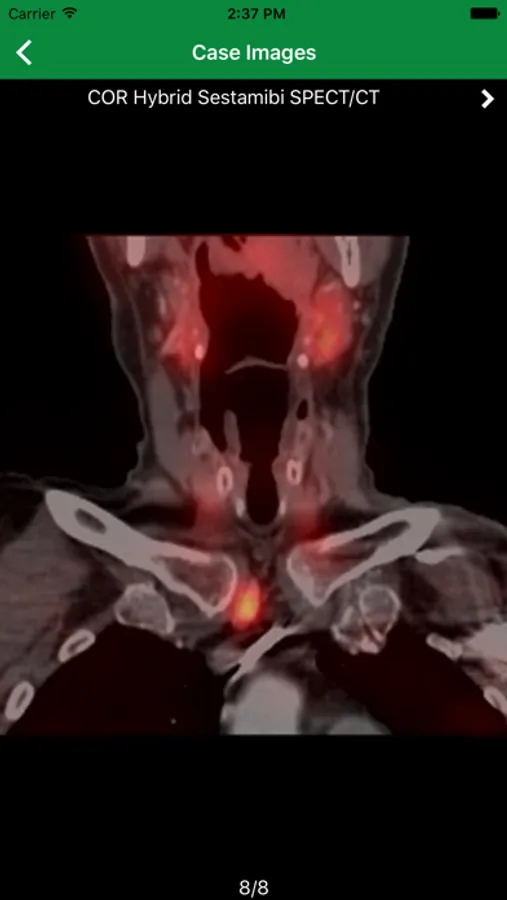

ARRS 2020 Screenshots